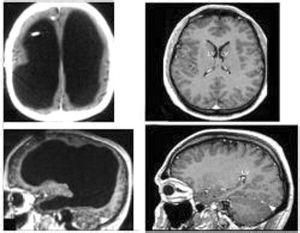

本病最顯著病理特點是在中樞神經系統的白質,圍繞血管周圍,尤其在小靜脈周圍可見髓鞘脫失,疾病早期,可見無數直徑約1mm的脫髓鞘病灶,廣泛分布於腦和脊髓的白質,以腦室周圍的白質,視神經和顳葉最明顯,軸索相對完整,血管周圍水腫且有明顯的炎性細胞浸潤,疾病晚期,病變周圍膠質細胞增生,瘢痕形成,一般說本病所有病灶的病理改變時相是相同的,反映本病屬臨床單時相疾病。